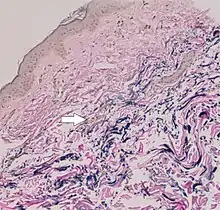

In PXE, there is mineralization (accumulation of calcium and other minerals) and fragmentation of the elastin-containing fibers in connective tissue, but primarily in the midlaminar layer of the dermis, Bruch's membrane and the midsized arteries.[26] Recent studies have confirmed that PXE is a metabolic disease, and that its features arise because metabolites of vitamin K cannot reach peripheral tissues.[27] Low levels of PPi cause mineralization in peripheral tissues.[19]

The diagnostic criteria for PXE are the typical skin biopsy appearance and the presence of angioid streaks in the retina. Criteria were established by consensus of clinicians and researchers at the 2010 biennial research meeting of the PXE Research Consortium.[29] and confirmed at the 2014 meeting[30] These consensus criteria state that definitive PXE is characterized by two pathogenic mutations in the ABCC6 or ocular findings – angioid streaks > 1 DD or peau d’orange in an individual <20 years of age together with skin findings:

- Diagnostic histopathological changes in lesional skin: Calcified elastic fibers in the mid and lower dermis, confirmed by positive calcium stain

| White fibrous papulosis of the neck | LM: Dermal fibrosis in papillary and mid-reticular dermis |